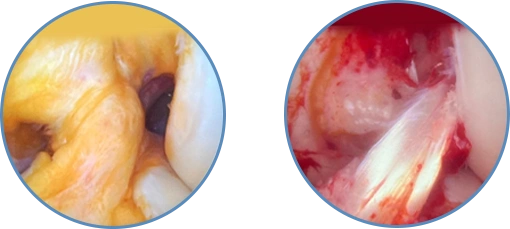

A artroscopia é um procedimento cirúrgico minimamente invasivo que utiliza um instrumento chamado artroscópio para visualizar e tratar lesões dentro da articulação do joelho.

O tratamento das rupturas tendíneas pode envolver diversos procedimentos cirúrgicos para reparar ou reconstruir os tendões lesionados. A artroscopia, um método minimamente invasivo, pode ser utilizada para visualizar e tratar lesões dentro da articulação, incluindo rupturas tendíneas. Em casos mais complexos, a reconstrução pode ser necessária, envolvendo a substituição do tendão danificado por enxertos de tecido autólogo ou sintético para restaurar a função e a estabilidade da articulação.